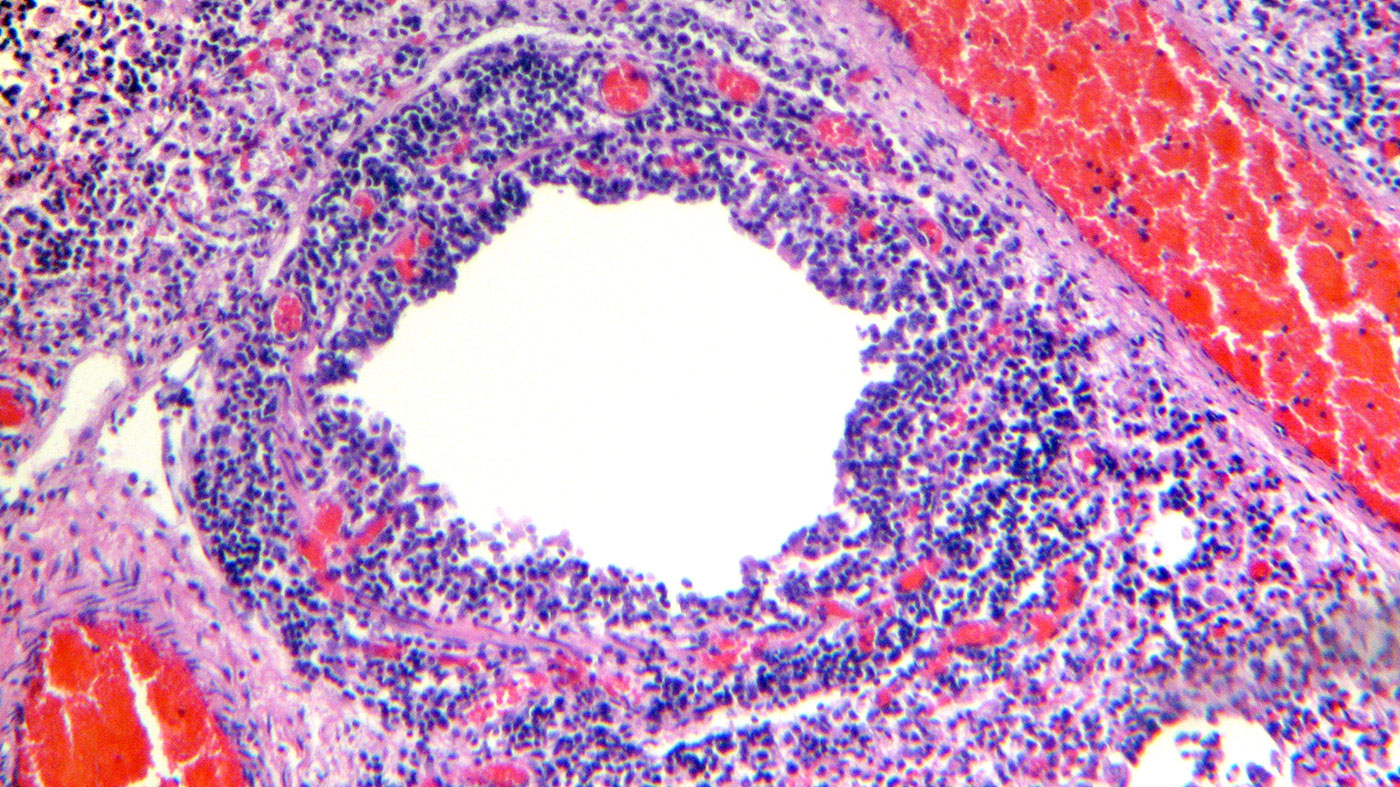

Examen histologique du tissu pulmonaire montrant une infiltration lymphocytaire de la lamina propria et de la sous-muqueuse bronchique (Figures 4 et 5).